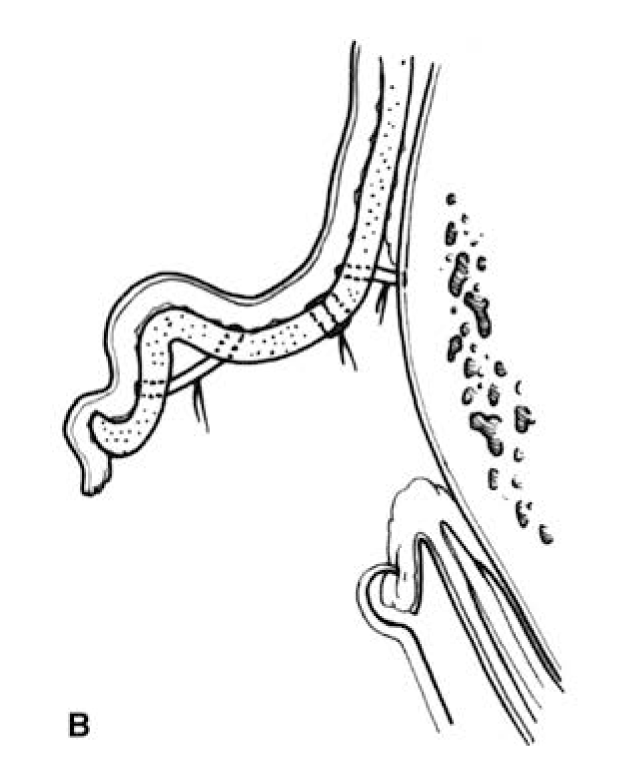

Macrotia. To reduce the size of the ears, an incision is made on the lateral surface of the ear, just inside the helical rim, through the skin and the cartilage, stopping short of the

medial skin (Figure 49.8). A crescent of scapha is removed. A segment of helical rim along with a triangle of medial skin is then excised and closed primarily, so that the helical rim is not redundant relative to the smaller scapha.7,8

FIGURE 49.8. Technique for reduction otoplasty. (With permission from Thorne CH, Wilkes G. Otoplasty, ear deformities and ear reconstruction. Plast Reconstr Surg. 2012;129(4):701e, Figure 2.)